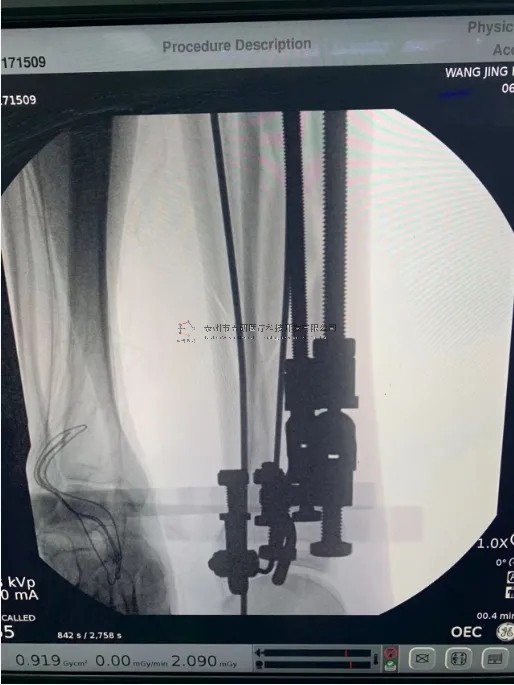

2月份,我們在中國中醫(yī)科學(xué)院望京醫(yī)院就有多臺關(guān)于外固定支架的手術(shù),以下介紹一則不開刀CO接骨治療小腿骨折典型病例:

【手術(shù)資料】